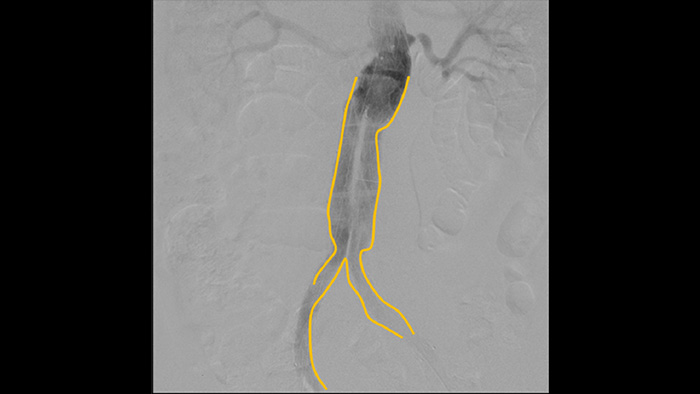

Digitale subtractieangiografie (DSA) wordt bij interventionele vasculaire procedures gebruikt om bloedvaten duidelijk te visualiseren door structuren die de zichtbaarheid van bloedvaten kunnen beperken te verwijderen. Roadmap-fluoroscopie overlapt eerder verkregen subtractiecontrastbeelden op live fluoroscopie, zodat u het instrument kunt volgen zonder opnieuw contrastmiddel te injecteren.

Contouren tekenen

Contouren knippen

Gebruik het hulpmiddel voor contouren knippen om eenvoudig een bifurcatie of zijtakken te markeren door simpelweg met uw vinger of een aangesloten muis op de monitor van het mobiele weergavestation te tekenen.

Superieure beeldkwaliteit en dosiscontrole van Zenition

Philips DoseWise Zenition is een unieke combinatie van technieken, programma's en praktijken, ingebouwd in onze Zenition mobiele C-boogsystemen, die tijdens elke toepassing klinisch relevante beeldkwaliteit bieden terwijl de dosis efficiënt wordt beheerd.

Voerdraden zijn gemakkelijker te zien dan bij ons oude systeem. U ziet nu de punt en de hoek van de draad die rondgaat, zelfs bij draden van 0,014 inch.

Dat komt doordat Zenition metaal en beweging compenseert.

Ramon Vila Coll

Arts in het universitaire ziekenhuis Bellvitge in Barcelona